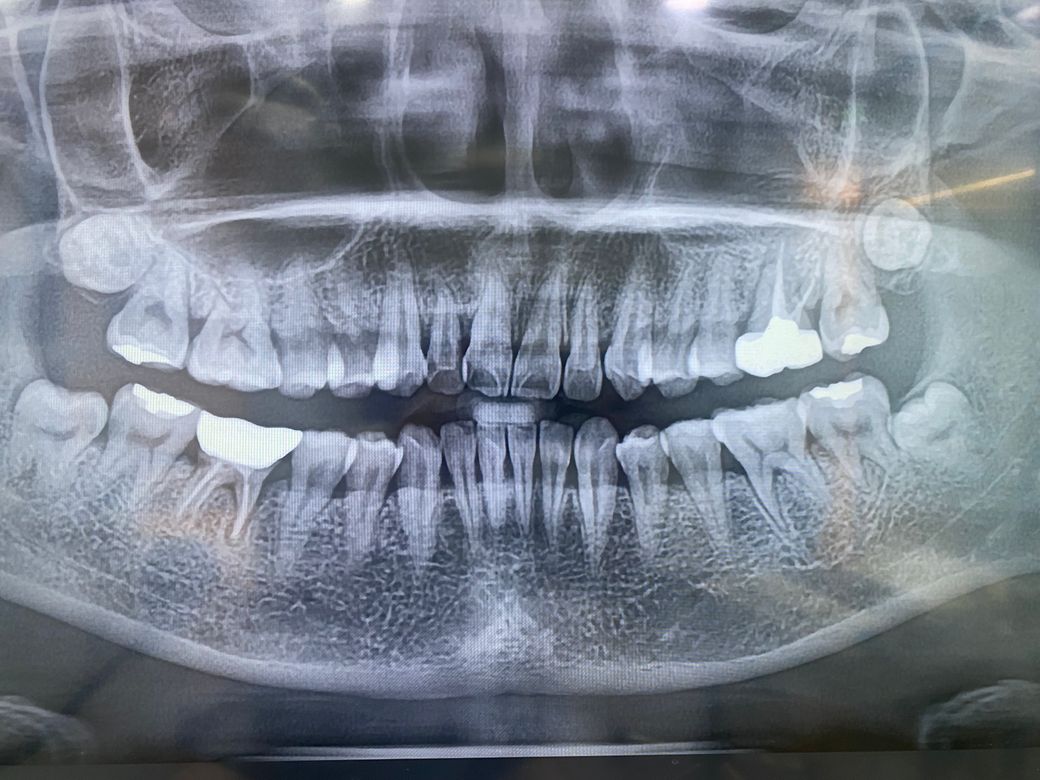

치료해야 할 충치처럼 보이나요????

치과의사들마다 전부 말이 다르네요

정지우식이라고 하고

누군 인레이 하라고 하고

누군 레진

현재 충치 치료가 필요로 되보입니다. 정지우식이라도 관리를 하지 않는 경우 진행이 되며, 양치를 꼼꼼히하여 관리가 필요로 됩니다. 우선은 충치가 발생한 부위를 치료를 받고 그후에 더이상 충치가 생기지 않도록 관리를 하길 권합니다.

현재 사진만으로는 판별이 불가능합니다. 충치를 직접 긁어보고 사진도 직접 봐야 알 수 있습니다.

사진으로 보기에는 정확한 확인이 어려워 보입니다.

치료여부의 충치를 확인하기 위해서는 치근단사진이나 육안과 촉진등의 검사가 필요합니다.

사진상으로는 치료를 해야될것같고 범위가넓어서 레진보다는 인레이를 하시는게 좋을것같습니다.